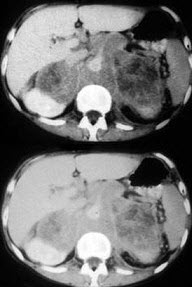

男,76岁,全身浅表淋巴结肿大,请结合下列图片作出诊断( )

A:肾上腺腺瘤

B:肾上腺癌

C:肾上腺嗜铬细胞瘤

D:肾上腺转移瘤

E:肾上腺淋巴瘤